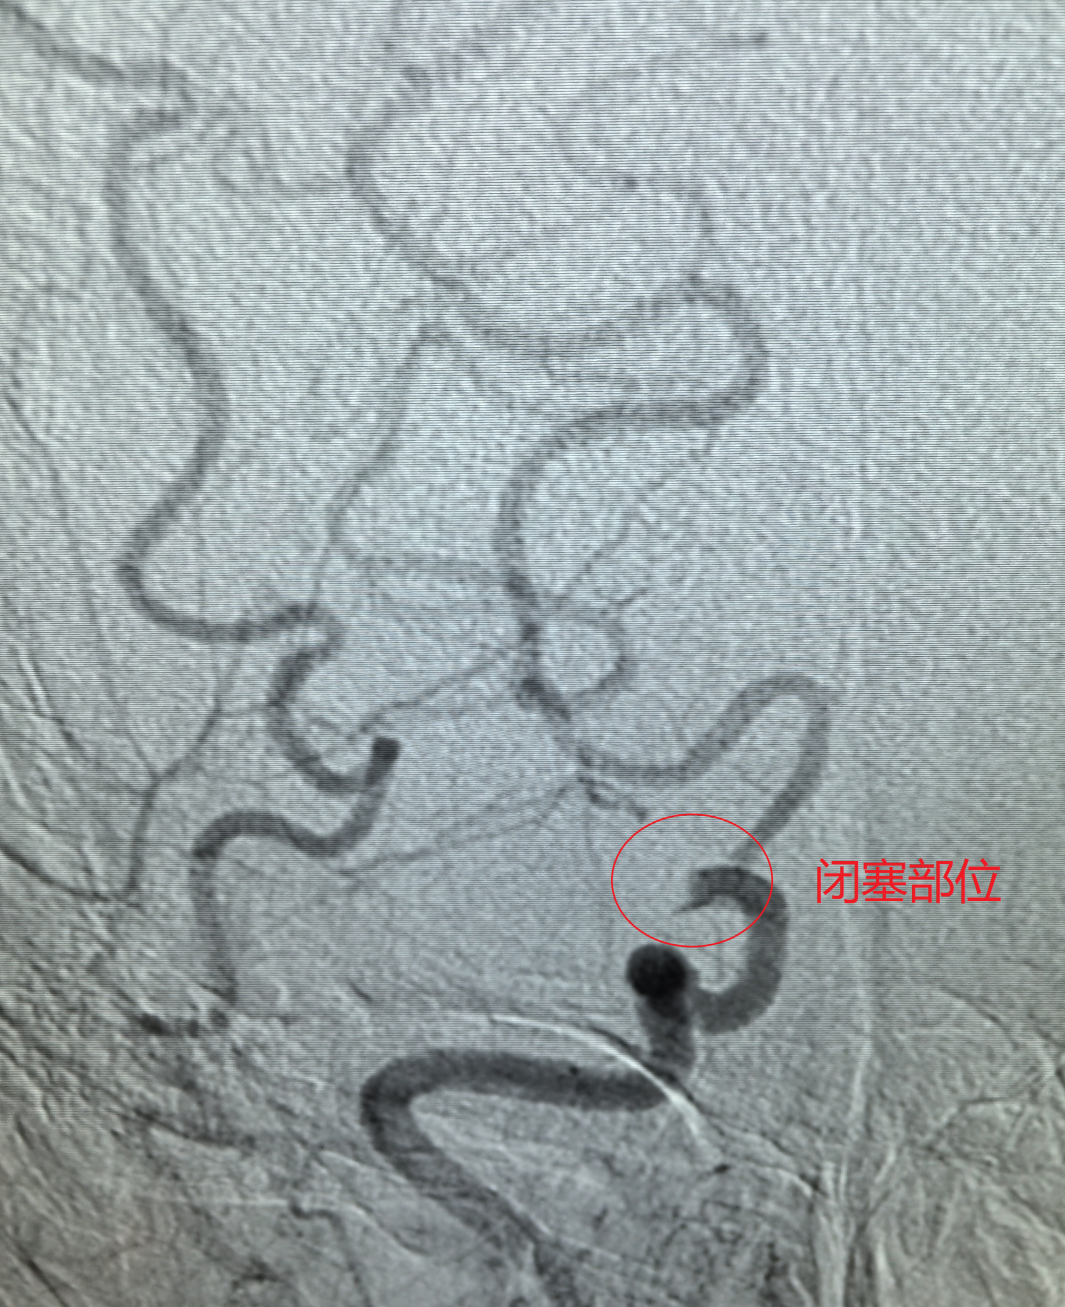

【技术领航】大脑中动脉“极细段”遭遇顽固血栓!市二院神经介入科精准取栓成功救治急性大面积脑梗死危重患者!

“精湛医术保健康,高尚医德为患者”!近日,一面承载着患者全家深深感激的锦旗,被赠送到葫芦岛市第二人民医院神经介入科钟强主任及陆阔医师手中。锦旗背后,是一场与死神赛跑的生命奇迹,钟强主任团队凭借高超的神经介入技术与多学科无缝协作,成功为一名急性大面积脑梗死危重患者施行高难度取栓手术,打通了被顽固血栓“死死封堵”的极细血管,最终助力患者获得良好康复。

挑战极限:“绣花功夫”疏通“生命狭道”